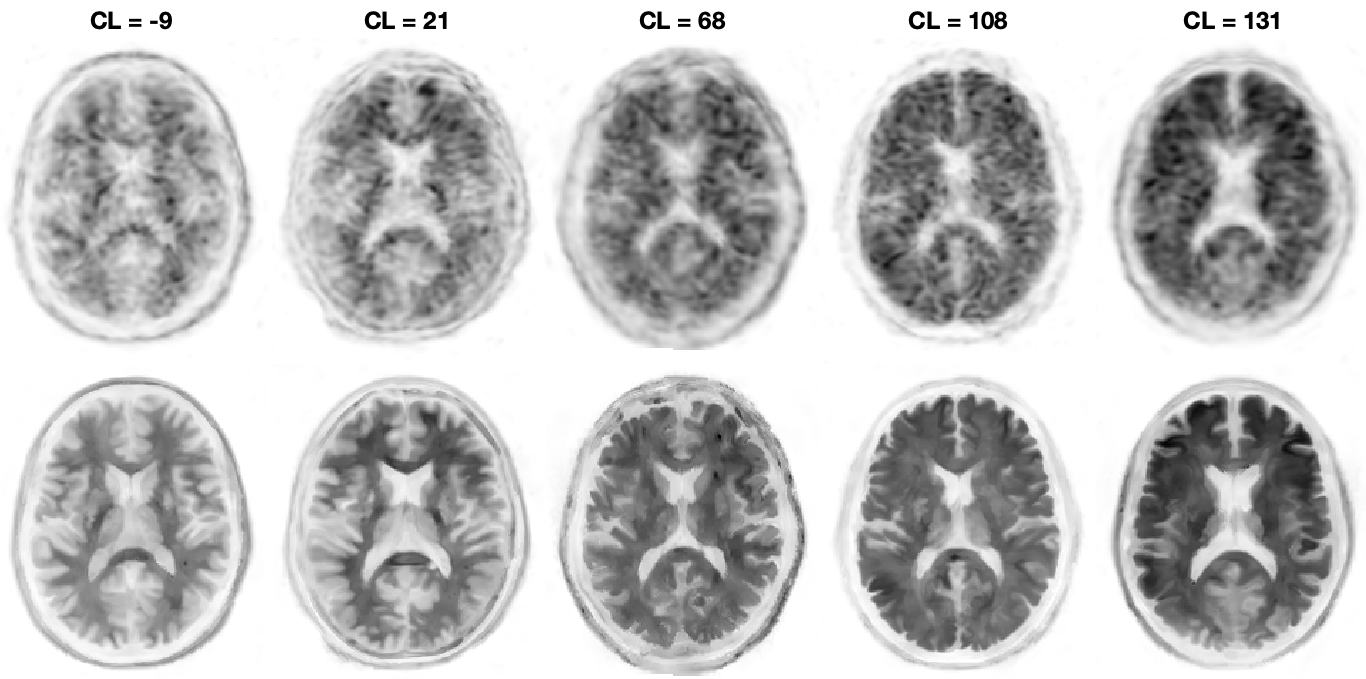

MICSI-PET is a turnkey upgrade that dramatically enhances PET image quality by using the MRI as an anatomical guide. This process does not require any additional imaging as all patients should have received an MRI prior to amyloid PET imaging. Operationally, this upgrade removes the primary barrier for scaling Alzheimer’s therapies by (1) enabling high-end PET imaging on low-end or aging PET scanners; (2) enabling shorter PET examinations leading to greater throughput; (3) minimizing ambiguity of positive/negative amyloid PET imaging by showing clearer boundaries between gray and white matter:

Figure: Coregistered conventional PET and MICSI-PET amyloid images across a range of amyloid burdens, highlighting differences in apparent cortical sparing: left, amyloid-negative with strong gray/white contrast; right, amyloid-positive with reduced gray/white contrast.